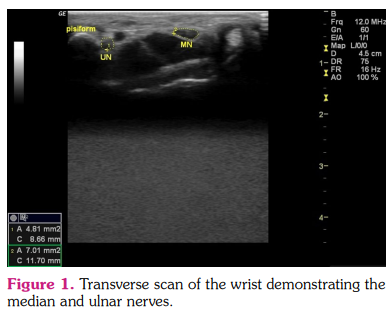

The age, sex, dominant hand, height, weight, disease duration, and medications were recorded. Patients were questioned for signs of CTS. Motor and sensorial examinations, Tinel’s test, and Phalen’s test were performed. Participants were evaluated in a sitting position facing toward the physician with the forearm in supine and rest position. All participants were evaluated with US (General Electric Logiq P5 device, 8-12 MHz high frequency transducer; General Electric Company, Boston, MA, USA) using the B mode by a physician blinded to patients’ characteristics. The US probe was held lightly not to apply excessive pressure and affect the anatomic structure of the nerves. The median and ulnar nerve CSAs were measured at the proximal inlet of the carpal tunnel using the pisiform as a bony landmark. The CSA was manually measured using the ‘manual trace’ program of the device, excluding the hyperechoic sheath (Figure 1). Each measurement was repeated three times, and the mean value was used in the analyses. The measurements of healthy controls and RA patients were compared.